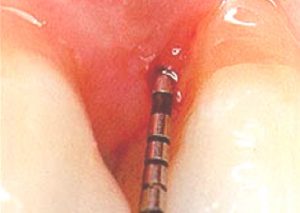

Periodontal Probe

A periodontal probe (small dental instrument) is gently used to measure the sulcus (pocket) between the tooth and the gums. The depth of a healthy sulcus measures three millimeters or less and does not bleed. The periodontal probe helps indicate if pockets are deeper than three millimeters. As periodontal disease progresses, the pockets usually get deeper. Your dentist or hygienist will use pocket depths, amount of bleeding, and tooth mobility to make a diagnosis that will fall into a category below: